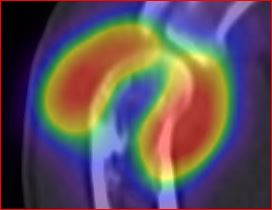

/ Obr.2.: SPECT/CT v koronárním řezu - zvýšený krevní pool v oblasti synoviální membrány pravého loketního kloubu.

/